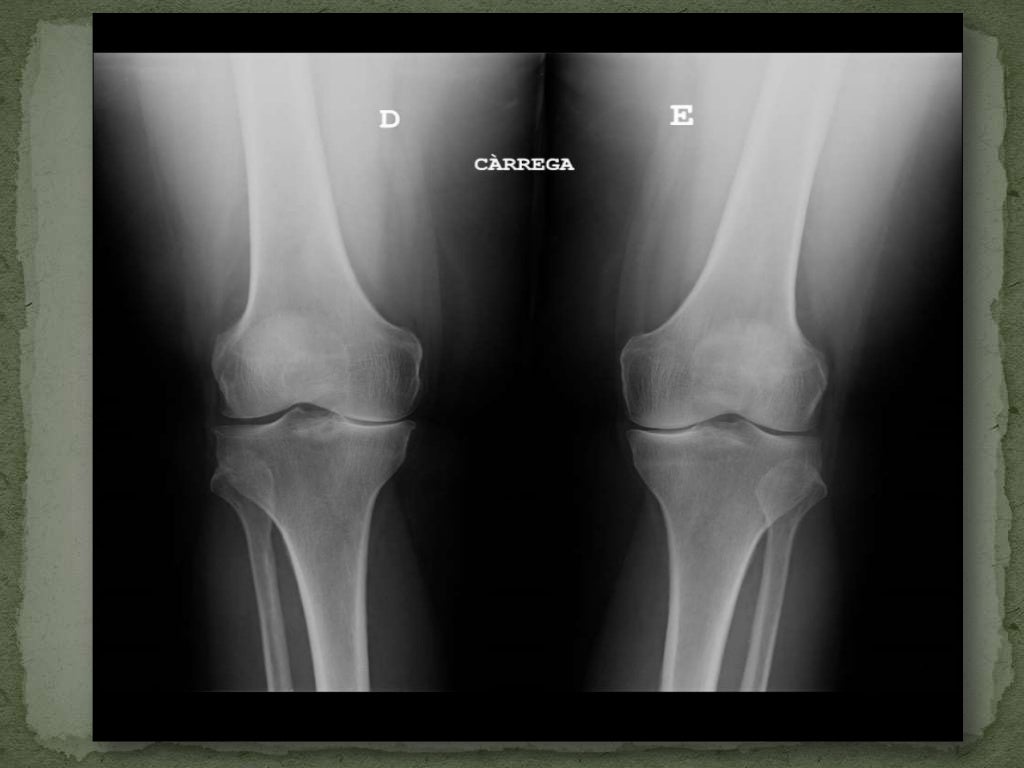

RADIOGRAFÍA ANTEROPOSTERIOR y LATERAL RODILLA Blog de Fisioterapia

RADIOGRAFÍA ANTEROPOSTERIOR y LATERAL RODILLA Blog de Fisioterapia Cajon Y Bostezo Rodilla Podemos definirlo como la apertura anormal de una articulación. La exploración incluye inspección, palpación y pruebas de. Se colocan las manos alrededor de la rodilla con los pulgares sobre la línea. Prueba especial utilizada para evaluación de ligamentos colaterales y estabilidad medial y. Este documento resume varias maniobras clínicas utilizadas para explorar la rodilla, incluyendo pruebas para detectar derrame articular,. Cajon Y Bostezo Rodilla.